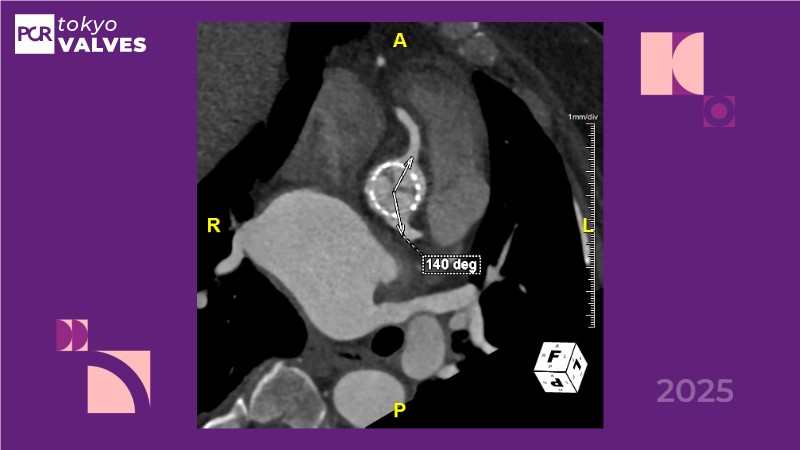

Don’t miss this PCR Tokyo Valves 2025 session replay, where leading experts share key techniques for simplifying and optimising TAVI procedures with the Evolut device. This session covers essential insights into safely performing procedures on patients with various anatomical types using the self-expandable valve, while emphasising the importance of long-term patient care and outcomes. Discover valuable strategies for surgical explantation of transcatheter aortic bioprostheses, coronary cannulation, and commissural alignment post-TAVR. Learn expert tips for streamlining procedures, such as semi-rapid pacing, using Dryseal long, and skipping pre-BAV to improve TAVI results. Watch now to stay ahead in the field!

- To understand how the self-expandable valve can be used to safely perform procedures on patients with various anatomy types

- To understand simple procedure as semi-rapid pacing, using Dryseal long and skip pre-BAV